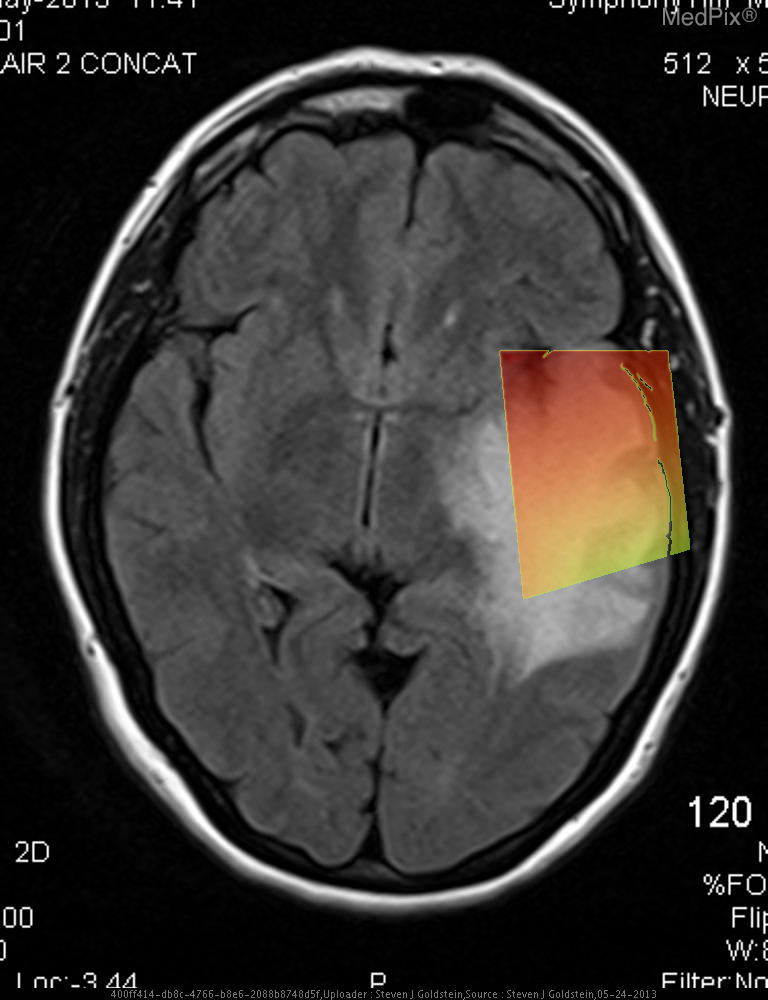

- A well-defined, extra-axial, dural-based mass is visible over the image-right (patient-left) frontoparietal convexity region.

- The lesion shows heterogeneously hyperintense signal intensity on this FLAIR MRI sequence.

- There is adjacent cortical sulcal effacement and underlying vasogenic edema extending into the adjacent white matter.

- Associated mild local mass effect with rightward (image-left, patient-right) midline shift is evident.

- The lesion margin appears broad-based against the inner table of the skull, with subtle dural thickening (“dural tail” sign possible).

- No hemorrhagic or cystic necrosis component clearly noted on this single sequence.

- Ventricles appear compressed on the image-right (patient-left) side due to mass effect.

- Cortical gray–white differentiation otherwise preserved outside the area of edema.

Extra-axial dural-based mass consistent with meningioma. The smooth, broad-based extra-axial location, dural attachment, and presence of vasogenic edema with mass effect are characteristic features of a meningioma. The rounded contour and preservation of cortical gray–white matter interface favor a meningioma over an intra-axial glioma. Context consistency: Consistent. The provided context indicates a 38-year-old female with “meningioma,” and imaging features align with this. Confidence: 90%.